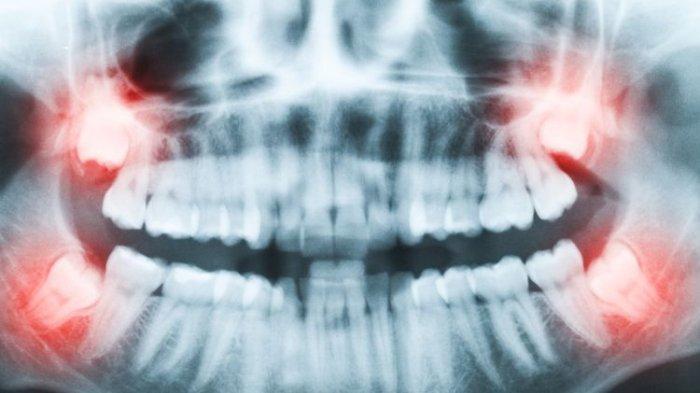

TRUBUNHEALTH.COM - Impaksi gigi bungsu adalah kondisi yang sering dialami oleh banyak orang, terutama mereka yang berada pada rentang usia 17 hingga 25 tahun.

Gigi bungsu yang tidak memiliki cukup ruang untuk tumbuh secara normal dapat menyebabkan rasa sakit, infeksi, dan kerusakan pada gigi-gigi lainnya.

Pemeriksaan gigi secara berkala dan penggunaan sinar-X dapat membantu memastikan bahwa impaksi gigi tidak menimbulkan masalah di kemudian hari.

4. Pencabutan Gigi Bungsu

Metode yang paling umum dan efektif untuk menangani impaksi gigi bungsu adalah pencabutan gigi.

Tindakan ini direkomendasikan ketika gigi bungsu yang impaksi menyebabkan rasa sakit, infeksi, atau kerusakan pada gigi di sekitarnya.